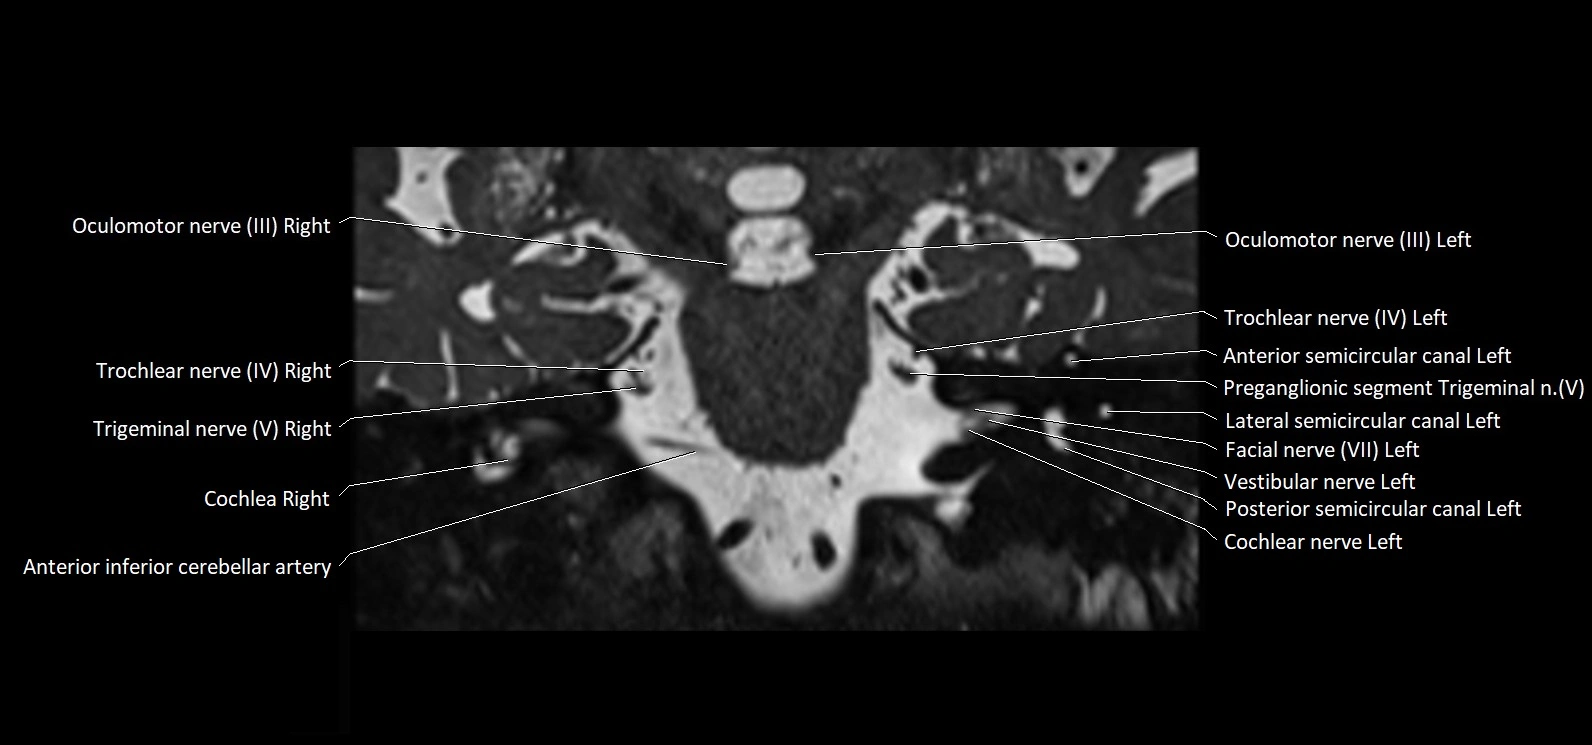

MRI Appearance

• The abducens nerve is a small, thin, linear structure

• Best visualized on high-resolution T2-weighted 3D MRI sequences (e.g., FIESTA or CISS)

• Seen as a hypointense (dark) line running from the brainstem at the pontomedullary junction, traversing the prepontine cistern, and entering Dorello’s canal under the petrosphenoidal ligament, then into the cavernous sinus, and finally the orbit

• May be challenging to visualize in standard MRI due to its small size

• Pathology may be inferred by absence, displacement, or enhancement of the nerve